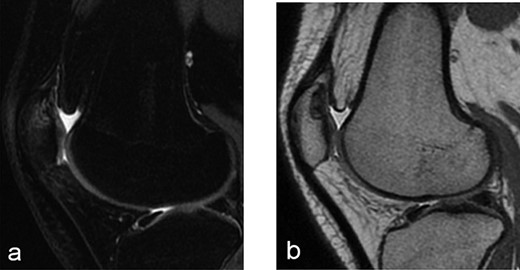

A 14-year-old female dancer presented with increasing right knee pain and functional disability without any trauma. Her pain was retropatellar pain that often radiated medially or laterally from the patella, exacerbated by climbing stairs, running and squatting. She was unable to perform any sports activities. Examination revealed peripatellar tenderness and crepitus, full range of motion and the knee was stable. Radiological examination included both MRI and computed tomography of the knee were performed at the beginning. MRI showed osteochondritis dissecans at the area at the superolateral facet of the patella in the deep subchondral area as shown in Fig. 1. This was appropriately treated conservatively with 6 months of reduced load and protected weight bearing without relief of symptoms. She quit sport activity for 2 years and then another MRI was performed Fig. 2. After 2 years we opted for adipose-derived mesenchymal stromal cells (AD-MSCs) intra-articular therapy according to the procedure described by Tremolada et al. [9]. The patient’s parents were given written information regarding the use of AD-MSCs therapy, including relative risks of this therapy and also relevant treatment alternatives that could otherwise be explored. Postoperative radiological evaluation was performed at 6 months and 12 months after AD-MSCs procedure as shown in Figs. 3 and 4. Postoperative clinical evaluation was performed using IDKC, Lysholm and Tegner scores (Table 1). After surgery, patients began a McConnell program of lateral retinacular stretching, patellar taping and vastus medialis obliquus muscle exercises. The patient was encouraged to swim and cycle to reduce impact loading. Using AD-MSC, she reported a complete relief of pain after 1 year from the procedure. Routine MRI follow-up 2 years later showed evidence of appreciable improvement in cartilage volume and osteochondral architecture at the site of injury. Early MRI T2 mapping at 6 months indicated that the area of cartilage regeneration exhibited high water content suggestive of immature cartilage or fibrocartilage morphology. Later T2 mapping at 18 months after the procedure, indicated progressive maturation of cartilage from deep to superficial layers with more hyaline like cartilage morphology. Limitations of the study are lack of arthroscopic intra-articular visualization and classification of the patella lesion.

Six months after MSC treatment in (a) axial and (b) sagital T2-weighted of MRI T2 sequences the OCD in patella showed that area of cartilage in regeneration and fill of high water content suggestive of immature cartilage or fibrocartilage morphology (c) same lesion in sagital T1 weighted MRI sequences.